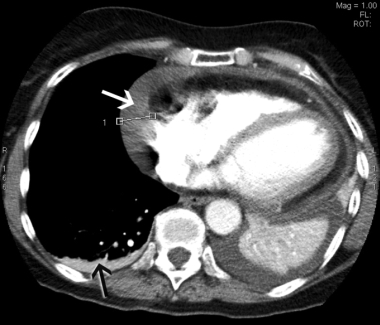

In view of the recent cholecystectomy, the patient underwent repeat CTPA, which excluded a pulmonary embolus but revealed a moderate pericardial effusion measuring up to 2.1 cm laterally and small bilateral pleural effusions (Box 2). An echocardiogram confirmed the pericardial effusion but showed no evidence of cardiac tamponade. Inflammatory markers were markedly elevated, with a C-reactive protein level of 290 mg/L (RR, < 12 mg/L) and an erythrocyte sedimentation rate of 103 mm/h (RR, < 21 mm/h). The patient had low-grade anaemia (haemoglobin level, 96 g/L; RR, 115–165 g/L), but this improved to 116 g/L without treatment. Her white cell count was elevated at 16 × 109/L (RR, 4–11 × 109/L), with predominant neutrophilia, and her platelet count was significantly elevated at 800 × 109/L (RR, 150–400 × 109/L). Renal function, urinalysis, autoimmune markers and a repeat troponin I measurement were normal. These findings were consistent with a diagnosis of Dressler’s syndrome.